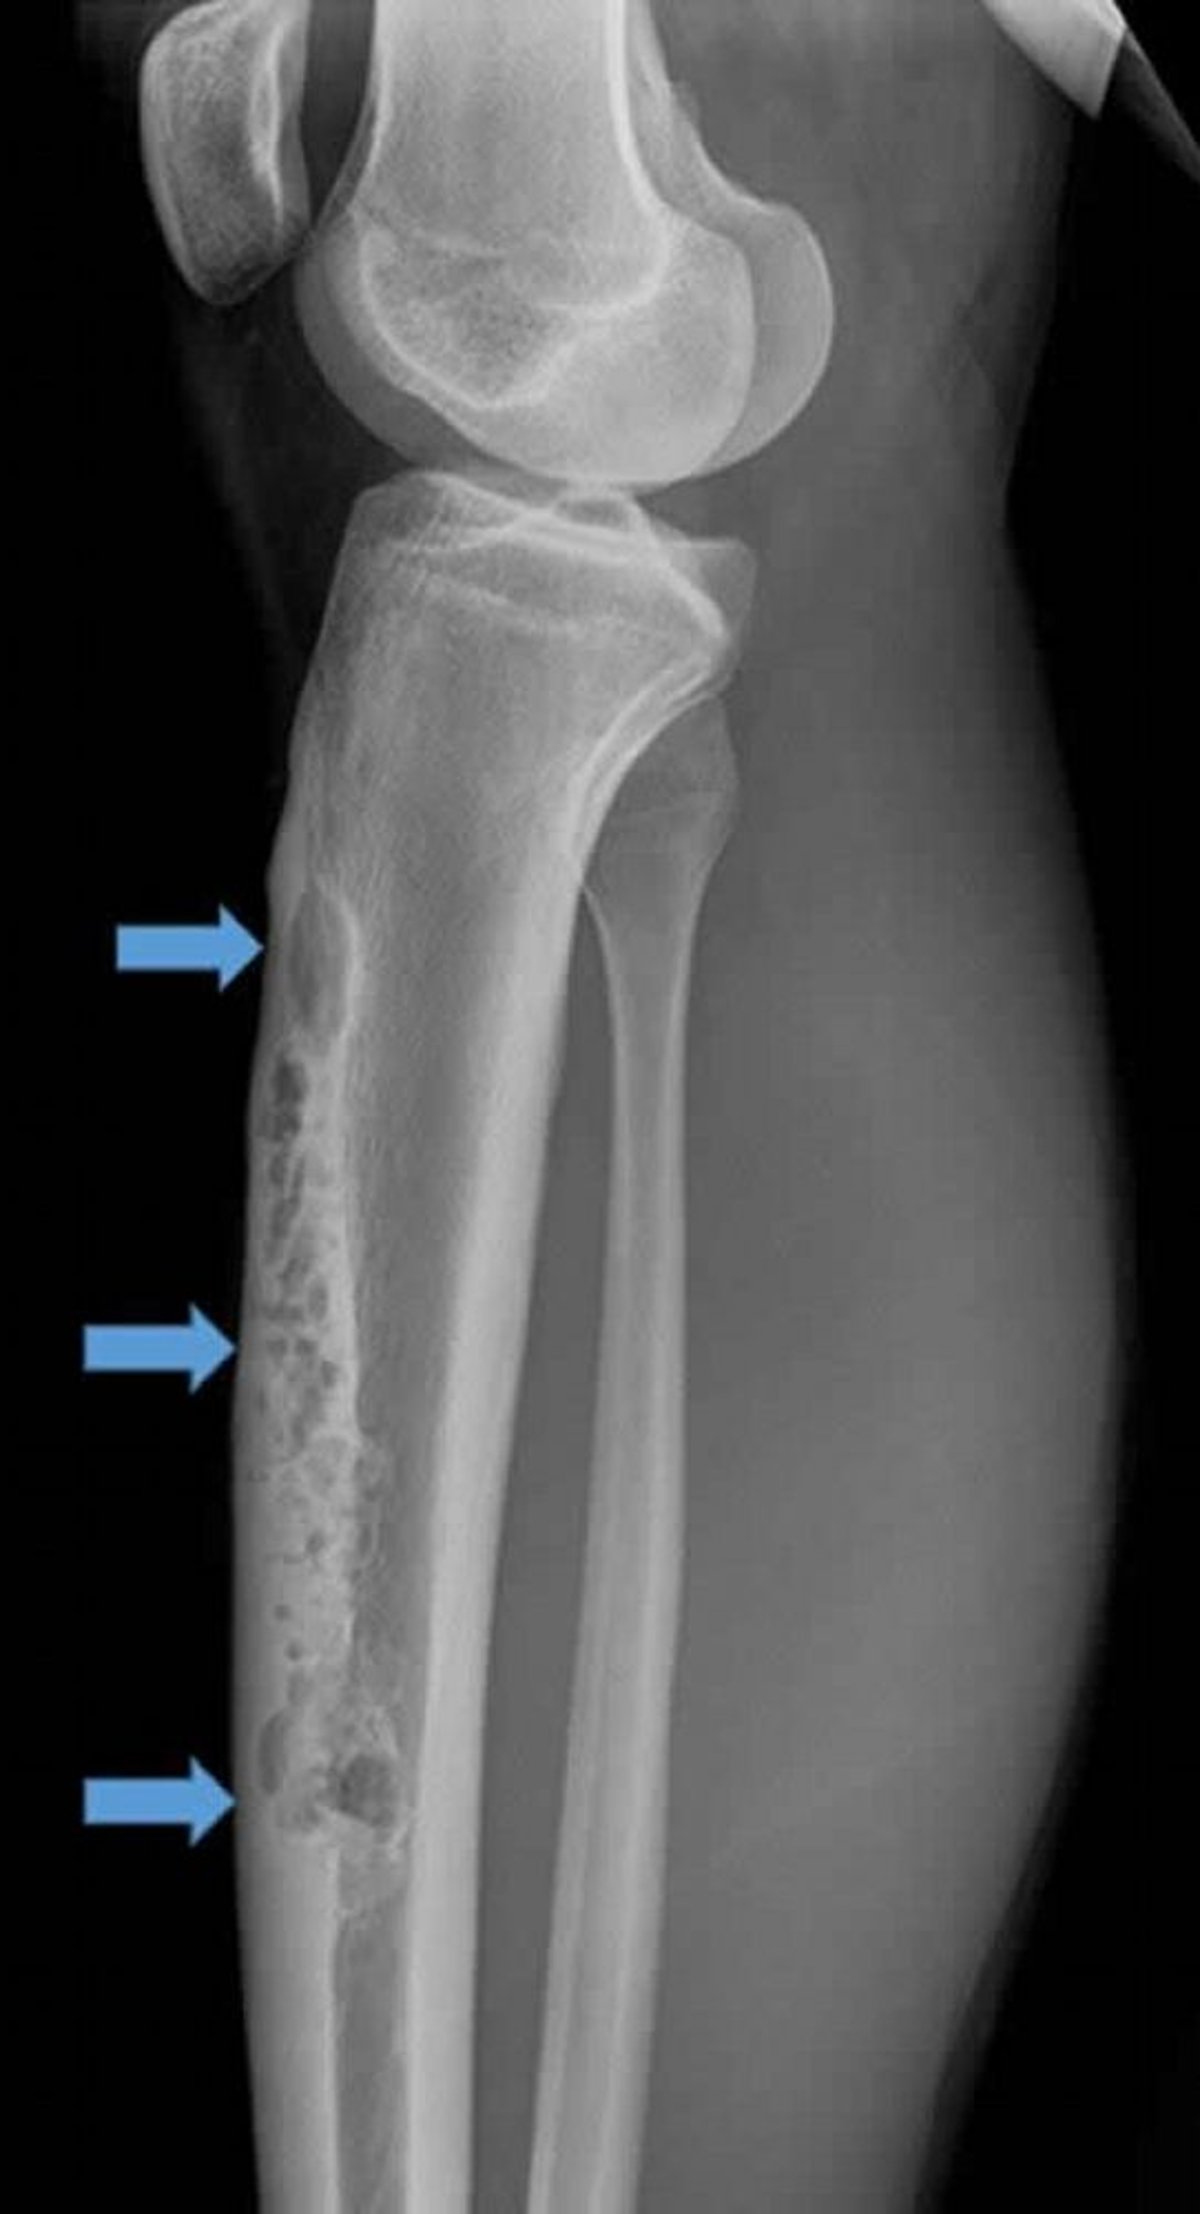

Адамантинома

На этой латеральной рентгенограмме правой голени показана большая внутрикортикальная адамантинома передней поверхности (стрелки). Обратите внимание на проникающий, остеолитический вид «мыльных пузырей».

Image courtesy of Michael J. Joyce, MD, and Hakan Ilaslan, MD.